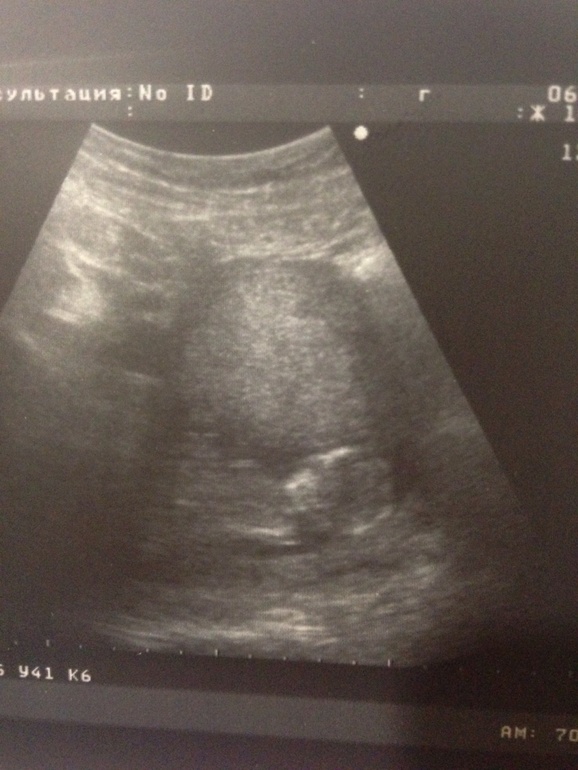

Сказать, что я переживала,- ну ничего не сказать! Переживания были в основном подсознательные : 2 ночи подряд я по раз десять ходила на скриниг ( во сне)))), а сегодня перед узи бешено колотилось сердце! Но все прошло просто замечательно)) ттт) увидела своего ребеночка) очень мило и трогательно) не буду мучатся с перечислением показателей и цифр) в общем мы рады и счастливы) фоточки под кат)))